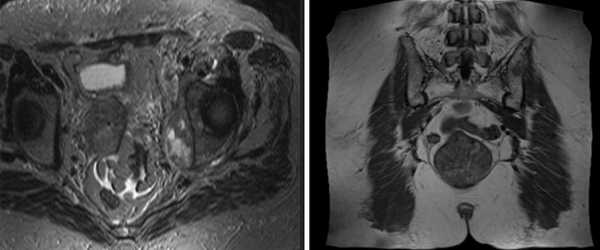

МРТ костей таза показывает множественные очаги, что говорит о метастатическом поражении

Магнитно-резонансное сканирование с контрастированием улучшает возможности визуализации. Исследование с усилением проводят для диагностики опухолевого процесса, включая обнаружение метастазов в костях таза, раннего выявления рецидива новообразования после лечения, уточнения степени выраженности воспалительного процесса, деструкции и пр. Контраст на основе гадолиния обладает высоким профилем безопасности и не требует предварительной оценки функции почек. Побочные эффекты на введение парамагнетика регистрируют крайне редко. В 99,9 % случаев исследование проходит без осложнений. Противопоказания к контрастированию: